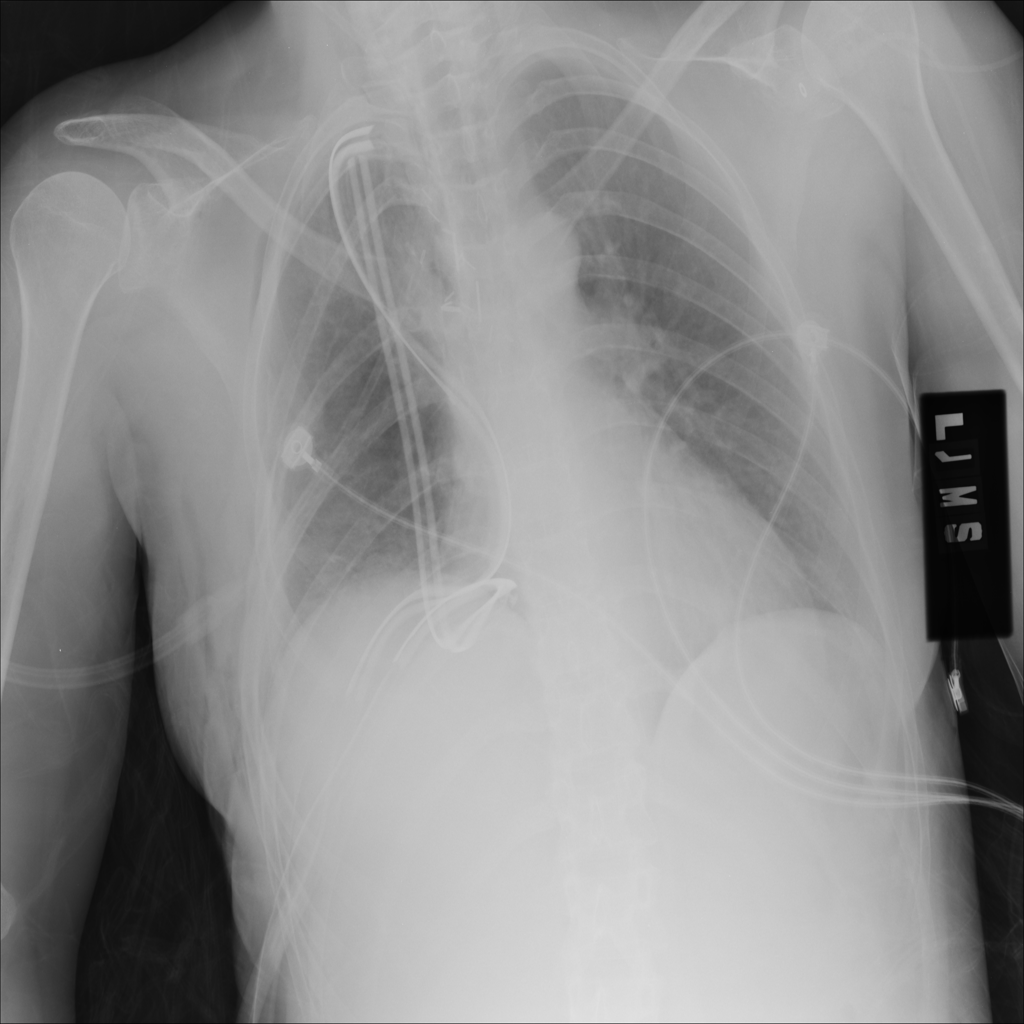

Showing up to 90 reference images for Emphysema.

PAT-B0DB · IMG-003Emphysema

PAT-B0DB · IMG-003

PA